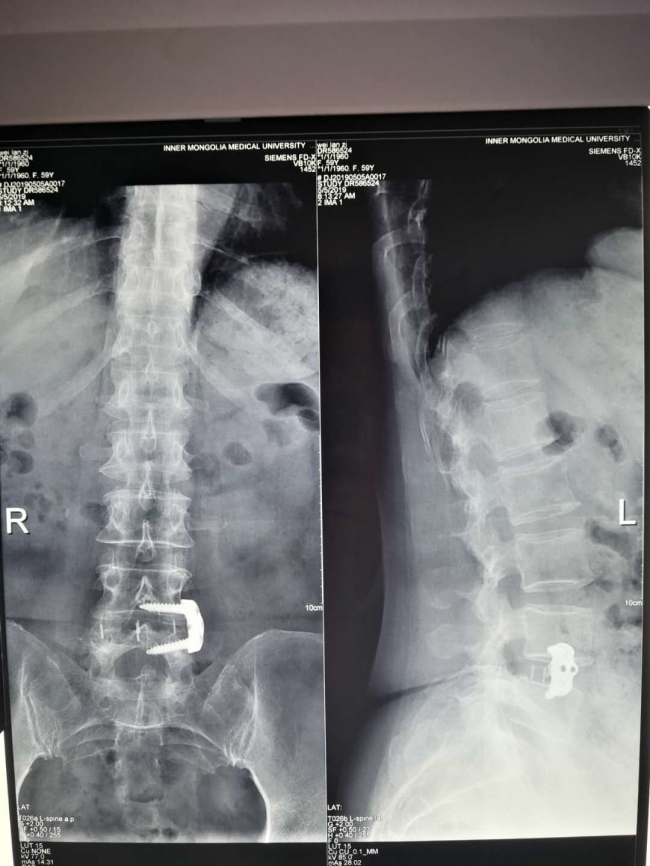

近日,我院微创脊柱外科成功为一名“腰椎不稳定继发腰椎管狭窄症”的59岁女性患者实施“OLIF”手术,为患者解除腰痛顽疾。

近年来,随着脊柱微创理念的更新以及微创技术不断发展,“靶点”治疗得到广大医学同道及患者的高度认可,常规脊柱手术逐步微创化、可视化、有限化及智能化。而OLIF(即斜外侧入路椎体间融合内固定术)治疗腰椎不稳定正是其中之代表。此项技术仅使用于腰椎不稳定伴或不伴轻度椎管狭窄,以及椎间盘源性痛的患者。此例手术皮肤切口约4cm,经腹膜外、腰大肌前缘入路,术中出血量仅为25mL。因其术中出血少,不干扰椎管内结构,对腰大肌及腰背肌无影响,无需引流,术后72小时即可下地活动,并发症发生率低,术后恢复快,住院时间短,治疗费用低,患者易于接受。